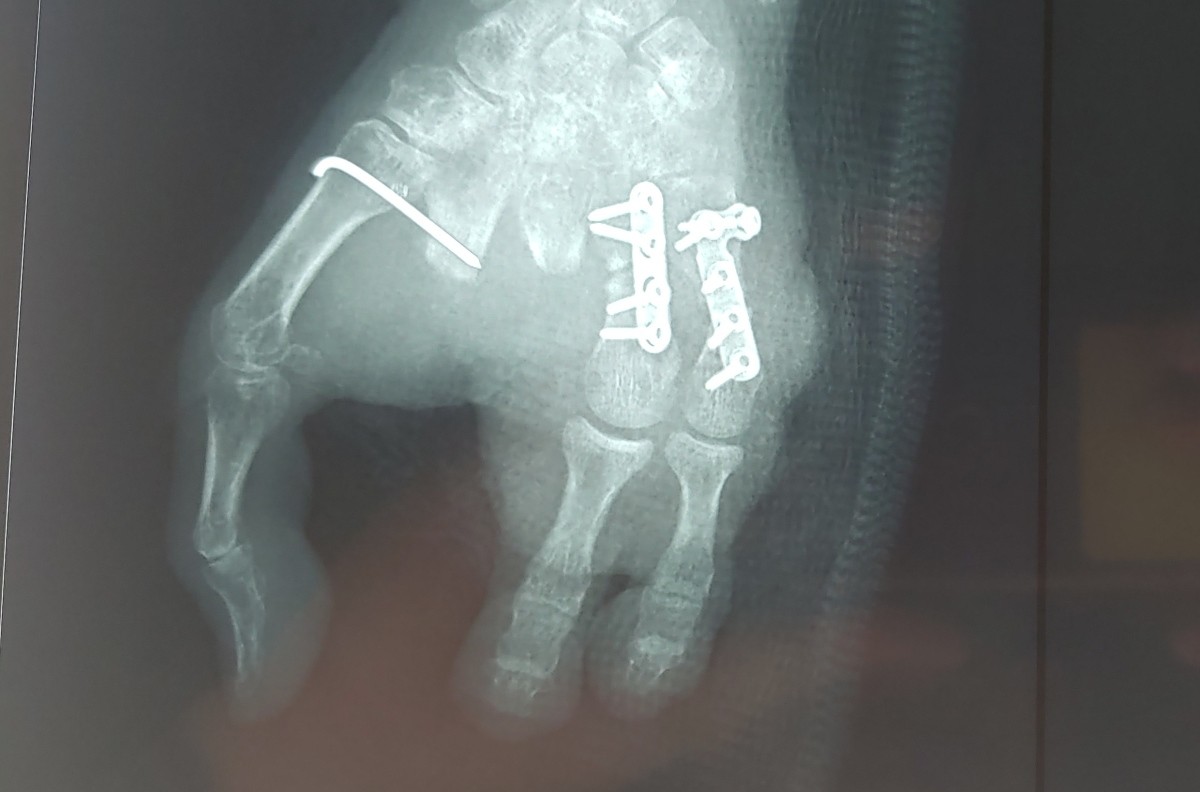

Ngày 5/1, bác sĩ Võ Thành Nhơn, khoa Phẫu thuật chi trên, Bệnh viện Quân y 175, cho biết ca phẫu thuật chuyển ghép hai ngón chân làm hai ngón tay kéo dài 6 giờ, bằng kỹ thuật nối vi phẫu gân mạch máu và thần kinh.

Ba tháng trước, người phụ nữ không may bị máy xay thịt cuốn nát 4 ngón tay trái không thể phục hồi, chỉ còn ngón cái nguyên vẹn. Các bác sĩ Bệnh viện 175 buộc cắt bỏ 4 ngón hỏng, tạo mỏm cụt để vết thương lành hẳn mới tính đến phương án phẫu thuật ghép chi.

Đến nay, phần mỏm cụt tay bệnh nhân ổn định, không có dấu hiệu nhiễm trùng, bệnh lý nền được kiểm soát tốt, các bác sĩ tiến hành ca ghép hai ngón chân thành hai ngón tay.